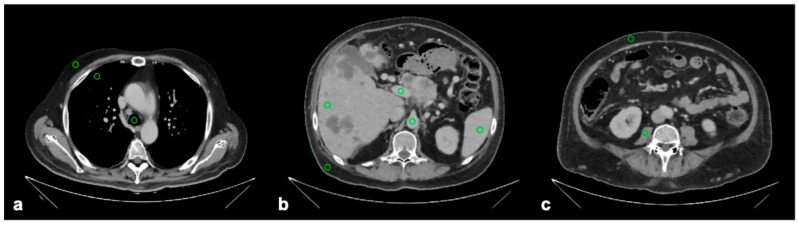

目的:本研究的目的是比较一种深度学习重建方法与现有的软组织CT图像重建方法的性能和鲁棒性。材料和方法:采用滤波后反投影、迭代模型重建(IMR)和深度学习重建(DLR),通过“标准”、“更清晰”和“更平滑”三个参数设置,对双层光谱检测器CT采集的门静脉期胸腹骨盆CT扫描(n = 99)进行图像生成。经验丰富的评分者通过考虑所有重建方法中十个代表性结构的衰减稳定性和图像噪声水平进行定量评估,并使用四点李克特量表(1 =差,2 =一般,3 =好,4 =优秀)对他们对“更平滑”的DLR和IMR图像的整体感知进行定性评估。一次扫描由于恶病质而被排除,这限制了定量测量。结果:定量测量的量表间信度为中等至优异(r = 0.63-0.96)。除腰大肌DLR与IMR的衰减值(平均+ 3.0 HU, p < 0.001)外,不同重建方法之间的衰减值无显著差异。图像噪声水平在所有结构的重建方法之间存在显著差异(均p < 0.001),并且在任何DLR参数设置下均低于FBP。“平滑”DLR的图像噪点水平主要低于或等于IMR,而“标准”DLR和“锐利”DLR的图像噪点水平则更高。“更平滑”的DLR图像在整体图像质量方面的平均评分高于IMR图像(3.7 vs. 2.3, p < 0.001)。结论:与FBP和IMR相比,经验丰富的读者认为“更平滑”的DLR图像质量更好,同时客观上也表现出更低或相当的噪声水平。

Objective: The objective of this study was to compare the performance and robustness of a deep learning reconstruction method against established alternatives for soft tissue CT image reconstruction. Materials and Methods: Images were generated from portal venous phase chest-abdomen-pelvis CT scans (n = 99) acquired on a dual-layer spectral detector CT using filtered back projection, iterative model reconstruction (IMR), and deep learning reconstruction (DLR) with three parameter settings, namely 'standard', 'sharper', and 'smoother'. Experienced raters performed a quantitative assessment by considering attenuation stability and image noise levels in ten representative structures across all reconstruction methods, as well as a qualitative assessment using a four-point Likert scale (1 = poor, 2 = fair, 3 = good, 4 = excellent) for their overall perception of 'smoother' DLR and IMR images. One scan was excluded due to cachexia, which limited the quantitative measurements. Results: The inter-rater reliability for quantitative measurements ranged from moderate to excellent (r = 0.63-0.96). Attenuation values did not differ significantly between reconstruction methods except for DLR against IMR in the psoas muscle (mean + 3.0 HU, p < 0.001). Image noise levels differed significantly between reconstruction methods for all structures (all p < 0.001) and were lower than FBP with any DLR parameter setting. Image noise levels with 'smoother' DLR were predominantly lower than or equal to IMR, while they were higher with 'standard' DLR and 'sharper' DLR. The 'smoother' DLR images received a higher mean rating for overall image quality than the IMR images (3.7 vs. 2.3, p < 0.001). Conclusions: 'Smoother' DLR images were perceived by experienced readers as having improved quality compared to FBP and IMR while also exhibiting objectively lower or equivalent noise levels.